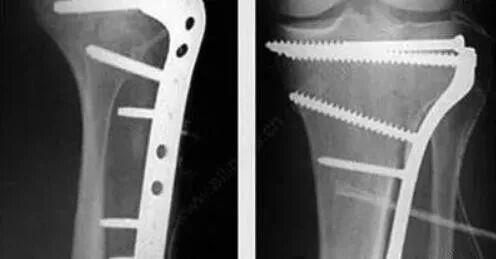

有些部位皮包骨头,比如肘关节、锁骨、踝关节、膝关节前方等,这里的骨折,放上钢板之后,皮肤下面就是钢板,很容易在日后发生问题。比如膝盖前方髌骨的内固定可能会影响到跪地的动作,而肘关节后方的钢板可能会在弯曲胳膊肘时顶到皮肤。所以这些皮包骨头部位的钢板如果已经产生了疼痛的症状,就要取出。就算现在还没有症状,但是预计在患者的预期生命里或者结合患者的自身工作性质可能以后会造成影响的,也应该取出。这种情况说明此处的软组织已经出现问题,很可能已经感染或者即将出现感染,如果X片显示骨折已经愈合,最好立即取出钢板,以便很好的控制感染。如果出现因为钢板影响到了关节的活动,应该尽早取出。否则时间久了,关节僵硬、增生、退变都会随之而来。

有些部位的骨头是形象外观的组成部分,比如锁骨,比如手掌骨指骨,比如踝关节,对于瘦的人来说,这些部位放上钢板后会凸出钢板的形状,可能会对某些爱美人士带来自信心和自我认同方面的影响。所以即使没什么疼痛症状,不妨取之。

比如腰椎颈椎,大腿股骨干、小腿胫腓骨、肩部的肱骨头、跟骨的钢板等,这些地方的钢板表面有厚厚的软组织覆盖保护,既不容易产生什么疼痛的症状,也不太影响外观,属于可取可不取的范畴。

取钢板前应认真清理钢板周围的骨痂,仔细核对螺丝钉的数目,务必全部取出; 钢板无明显骨痂包裹,螺丝钉全部取完后钢板仍难取出时要注意钢板原来没有上螺丝钉的钉孔部位,最易被瘢痕缠绕包裹,切断缠绕钢板的斑痕组织,即可取下钢板。